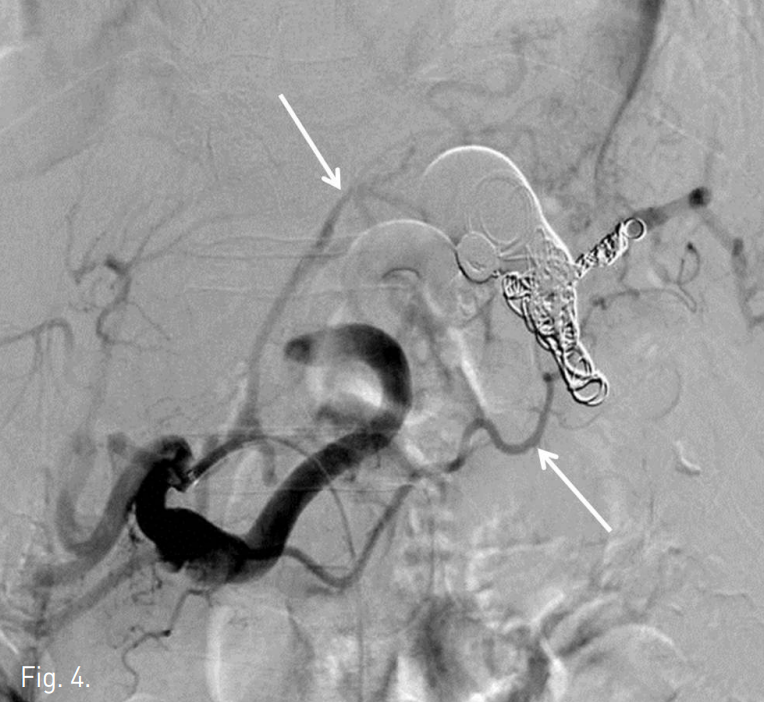

Fig. 4

Post-embolization arteriogram shows complete embolization of the aneurysmal sac. Distal part of the splenic artery is opacified through collateral flow (arrow).